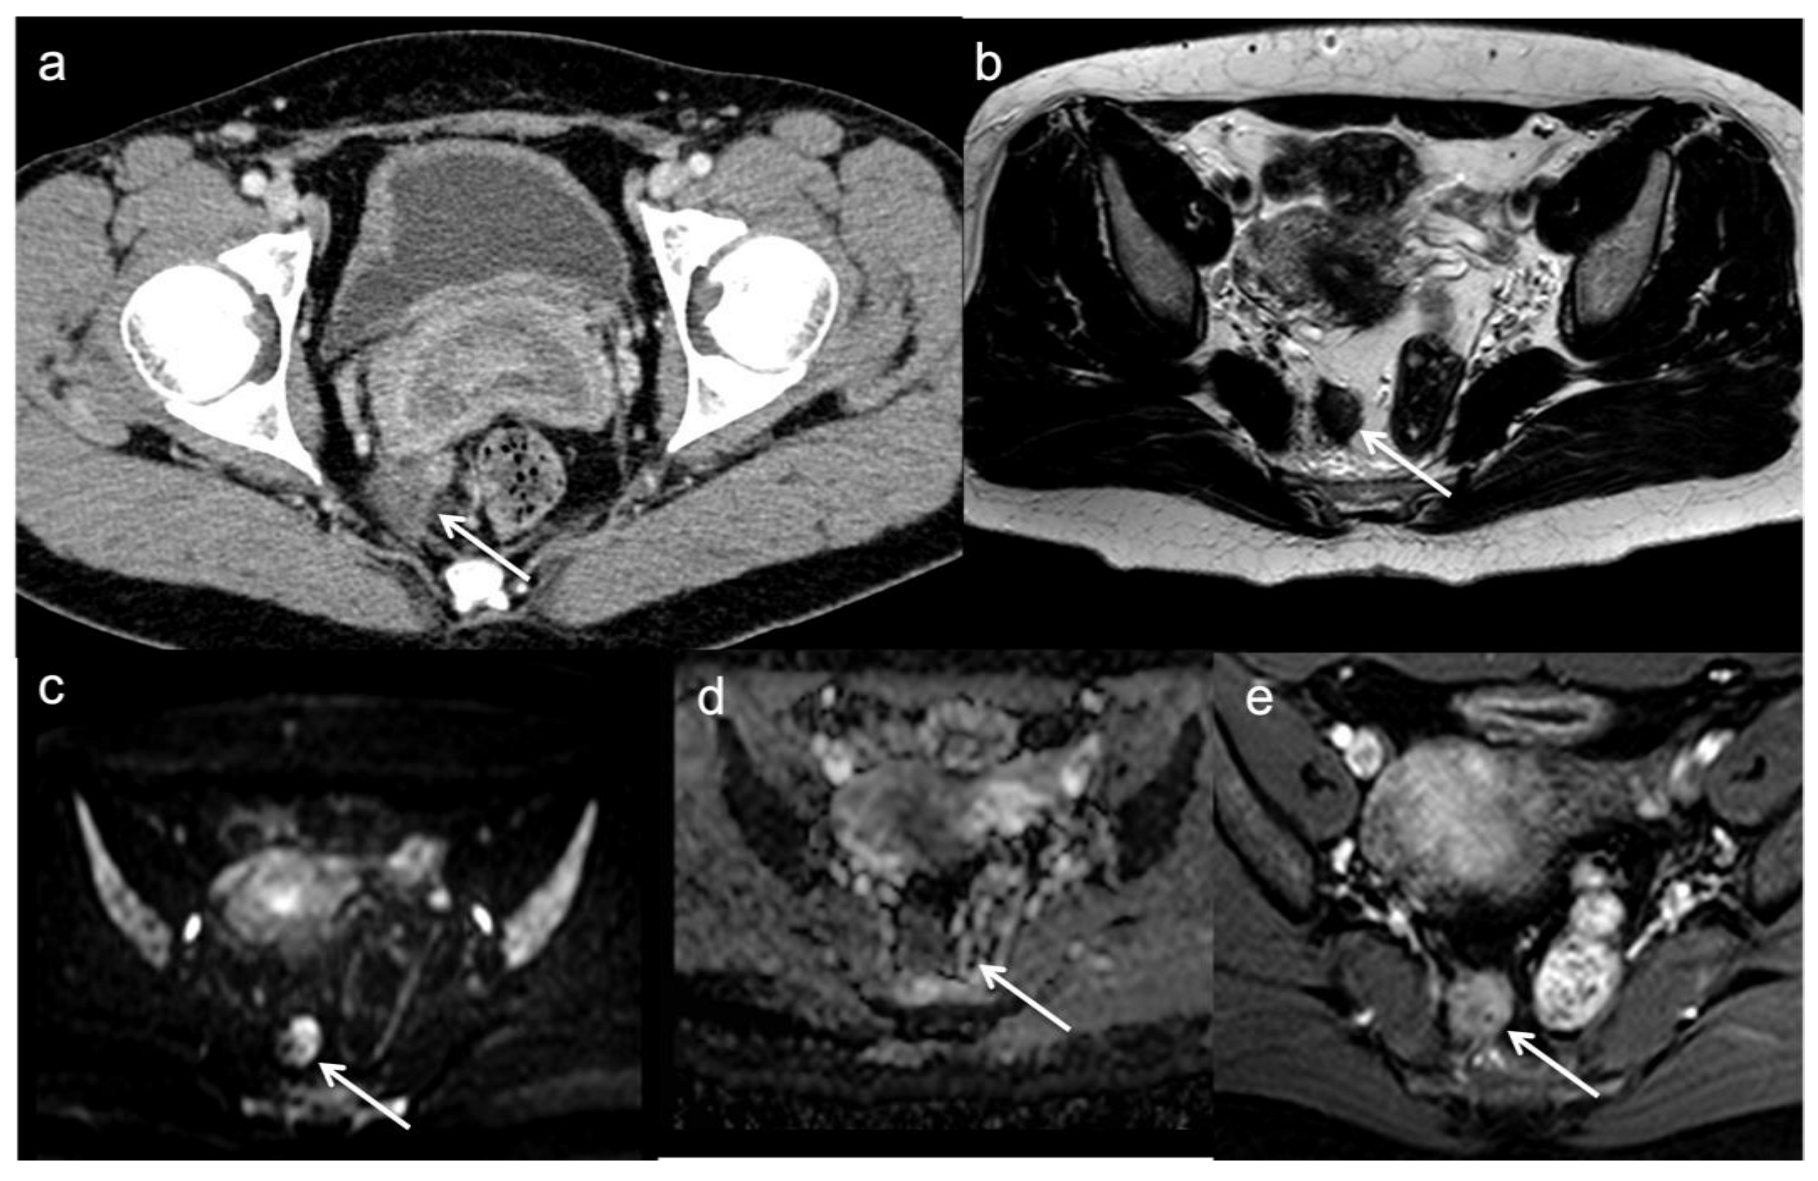

- Molinelli, V.; Angeretti, M.G.; Duka, E.; Tarallo, N.; Bracchi, E.; Novario, R.; Fugazzola, C. Role of MRI and added value of diffusion-weighted and gadolinium-enhanced MRI for the diagnosis of local recurrence from rectal cancer. Abdom. Radiol. 2018, 43, 2903–2912. [Google Scholar] [CrossRef] [PubMed]

- Lambregts, D.M.J.; Cappendijk, V.C.; Maas, M.; Beets, G.L.; Beets-Tan, R.G.H. Value of MRI and diffusion-weighted MRI for the diagnosis of locally recurrent rectal cancer. Eur. Radiol. 2011, 21, 1250. [Google Scholar] [CrossRef] [PubMed]

- Colosio, A.; Soyer, P.; Rousset, P.; Barbe, C.; Nguyen, F.; Bouché, O.; Hoeffel, C. Value of diffusion-weighted and gadolinium-enhanced MRI for the diagnosis of pelvic recurrence from colorectal cancer. J. Magn. Reson. Imaging 2014, 40, 306–313. [Google Scholar] [CrossRef]